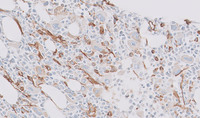

Figure 3: CD34 immunostain in CML–accelerated phase

Multiple images demonstrating several areas with increased numbers of CD34 positive blastic cells.  The cells reached up to 10% in some areas.  Occasional megakaryocytes demonstrate weak abnormal staining for CD34 noted on the image in the right.